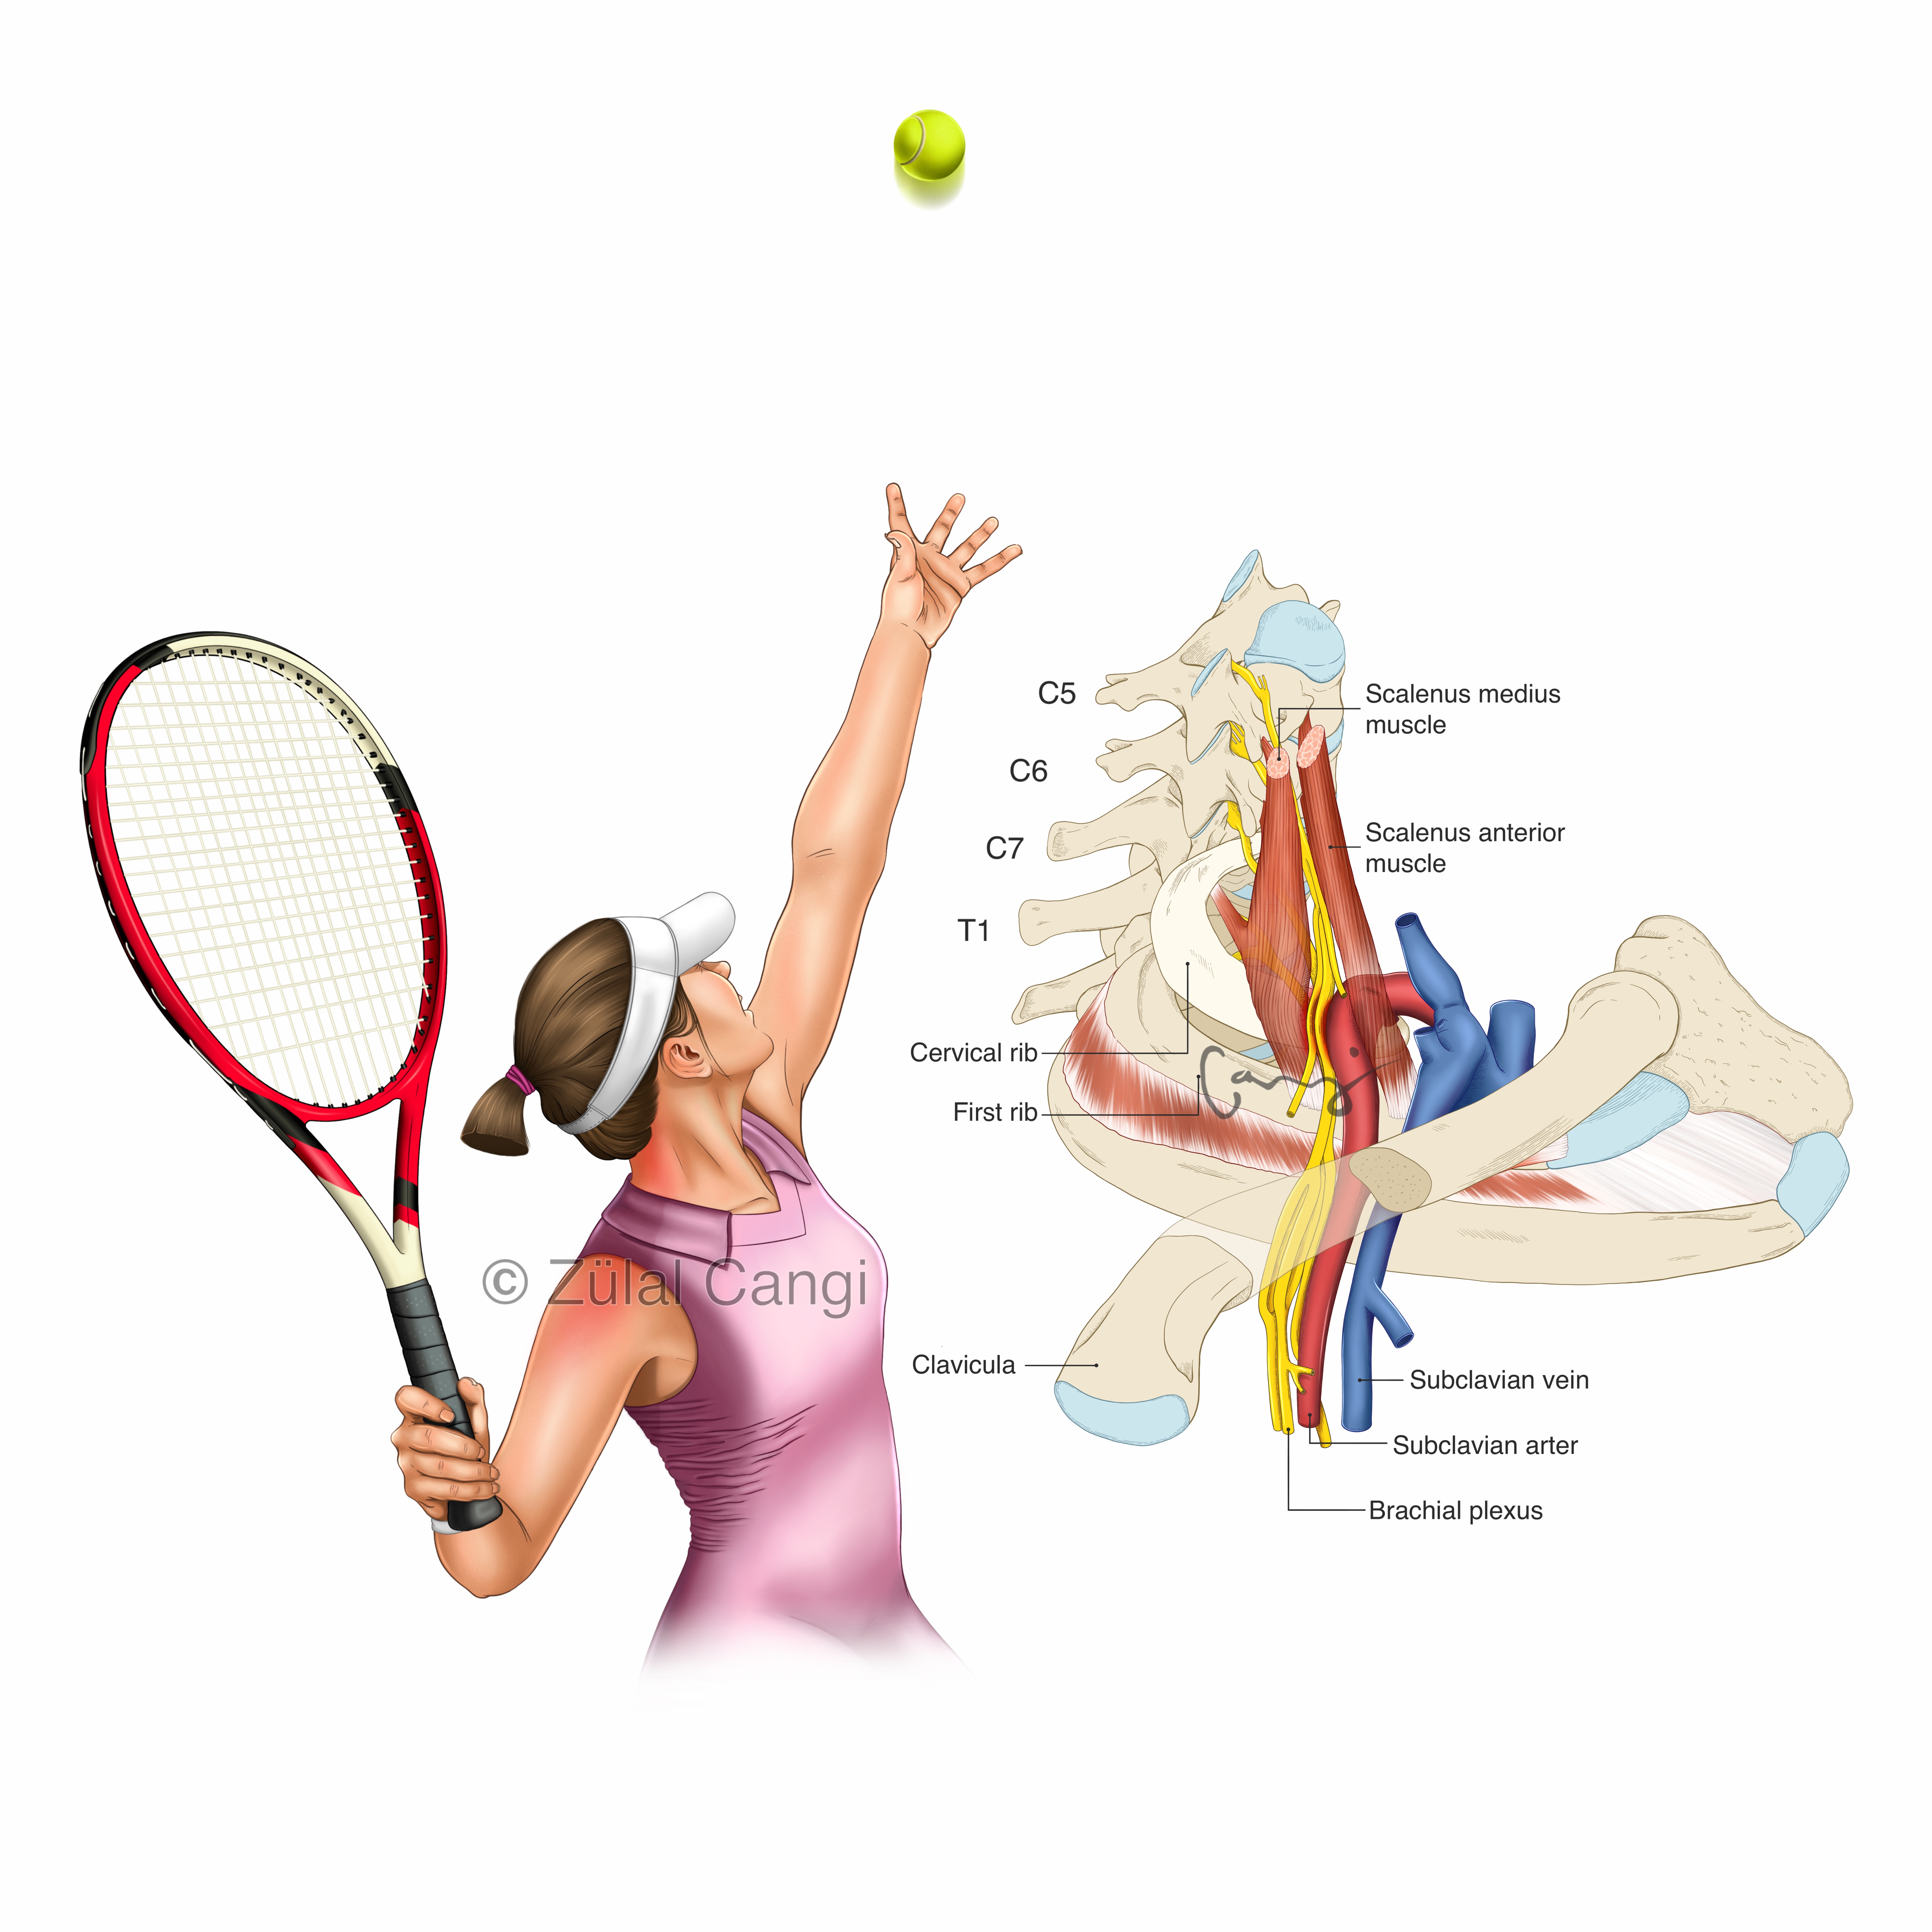

Sanatın estetiğini bilimin kesinliğiyle bir araya getiren Zülal Cangi, medikal ve bilimsel illüstrasyon alanındaki çalışmalarıyla akademik yayınlar, eğitim materyalleri ve çeşitli bilimsel platformlar için görsel içerikler üretmektedir. Amacı, bilimsel bilgiyi yalnızca doğru biçimde aktarmakla kalmayıp, aynı zamanda öğretici ve estetik bir dille görünür kılmaktır.

PORTFÖY